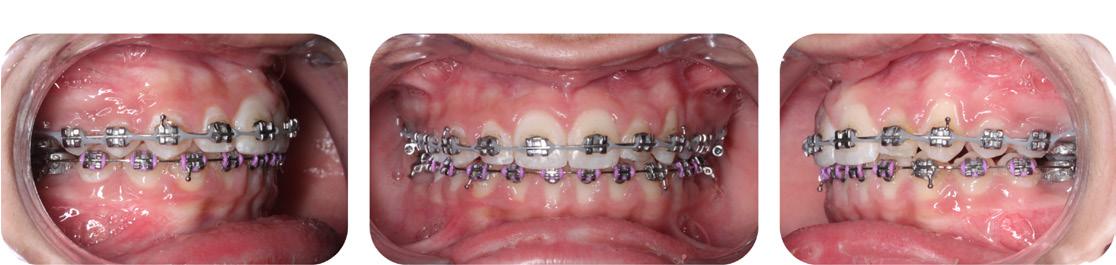

Clinical dental appraisal revealed full Angle Class II molar and cuspid relationship. The arches were wide and there was a moderate crowding. The patient had 9.0 mm overjet and 6.0 mm overbite. However, the patient reported SDB symptoms, and he also presented with symptoms and signs of TM dysfunction (Figure 4A, B, C, D, E, F))

FIG. 4A: Pre-treatment, frontal view

FIG. 4B: Pre-treatment, right lateral view

FIG. 4C: Pre-treatment, left lateral view

FIG. 4D: Pre-treatment, maxilla, occlusal view

FIG. 4E: Mandible occlusal view

FIG. 4F: Pre-treatment, OB and OJ